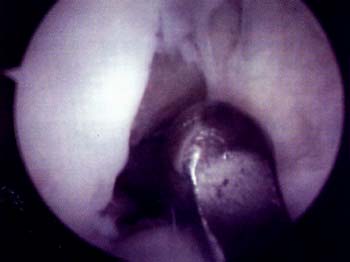

Foto 2: Vista artroscopica del Cruentado capsulo-sinovia interno.

Los pacientes en los que fracas6 el tratamiento incruento se les realize tratamiento artroscopico liberandose el retinaculo lateral y un retensado del retinaculo medial con cuatro o cinco puntos con material reabsorbible. La liberacion se efectuo con electrobisturi y no se coloco hemosutor en ninguno de los casos. El retensado interno se realize por una incision artroscopica ulnica medial de 5 a 8 mm, con una sutura reabsorbible de polidioxanona. En todos los casos se constato una realineacion clinica y artroscopica intraoperatoria.